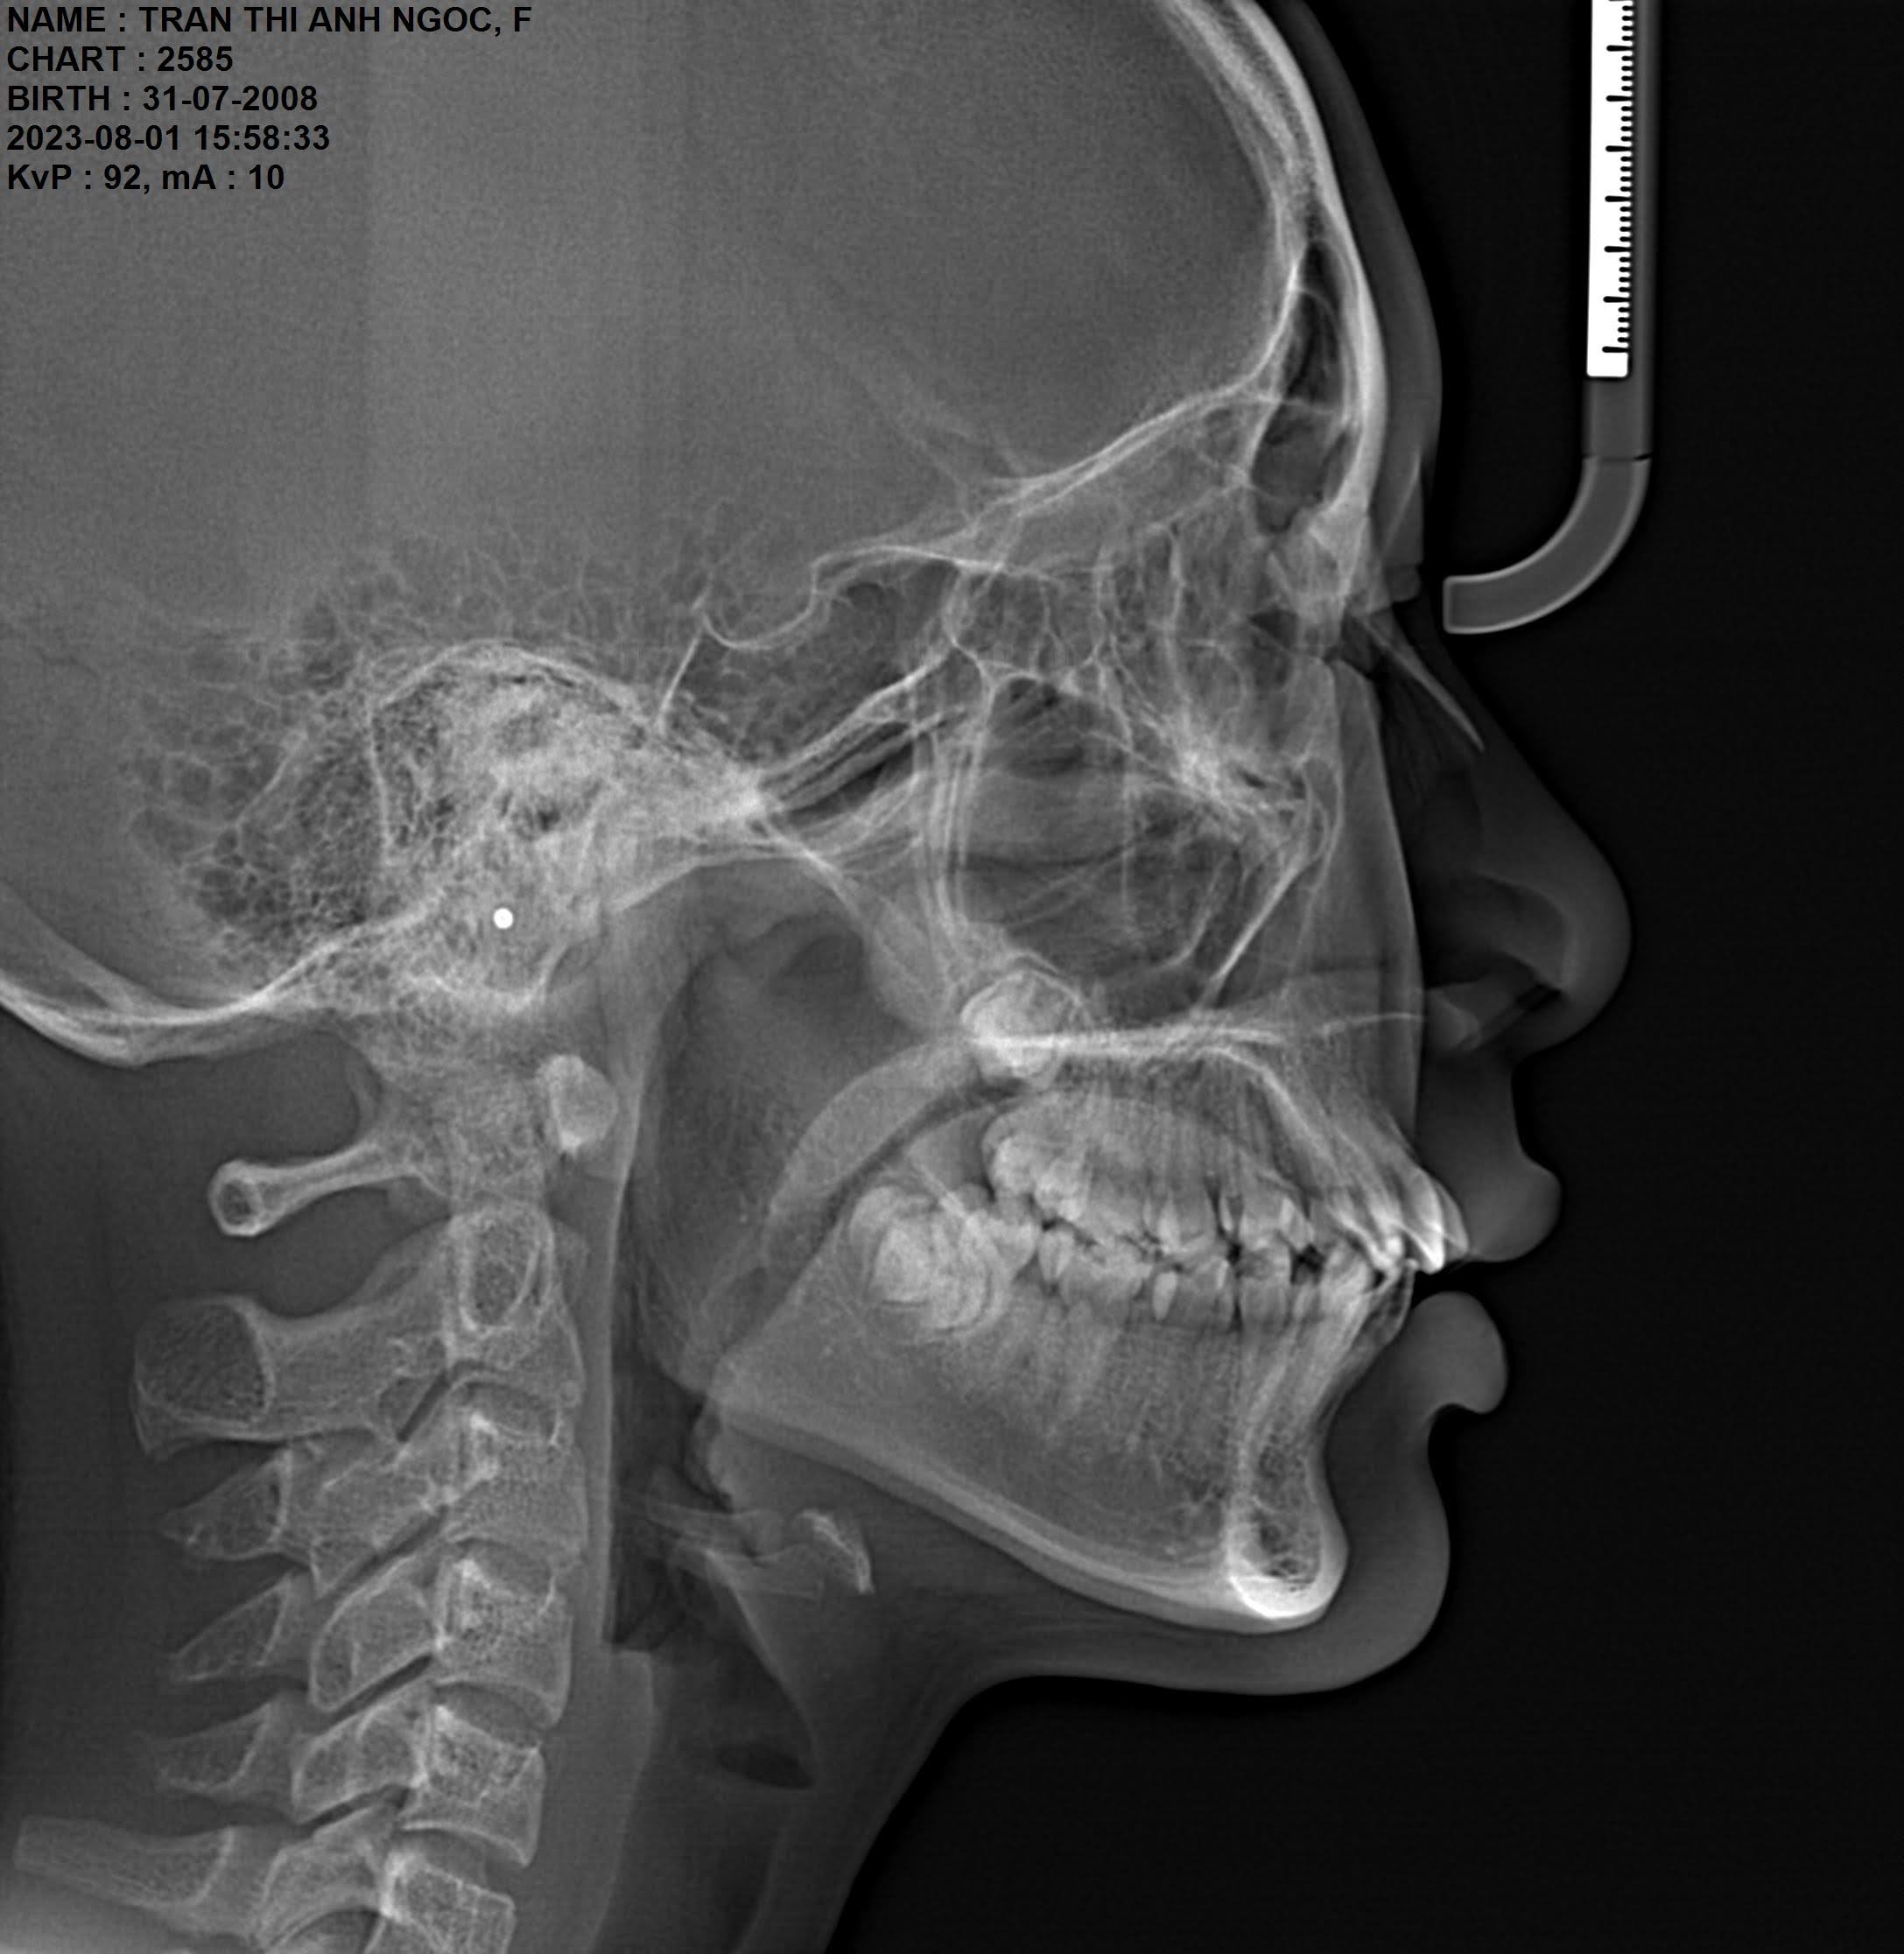

Chụp phim X-quang Cephalometric

Phim Cephalometric mang lại nhiều lợi ích giúp bác sĩ:

- Phân tích chi tiết cấu trúc xương hàm, góc nghiêng gương mặt

- Đánh giá mối tương quan giữa các răng

- Hỗ trợ tối ưu trong việc lập kế hoạch chỉnh nha